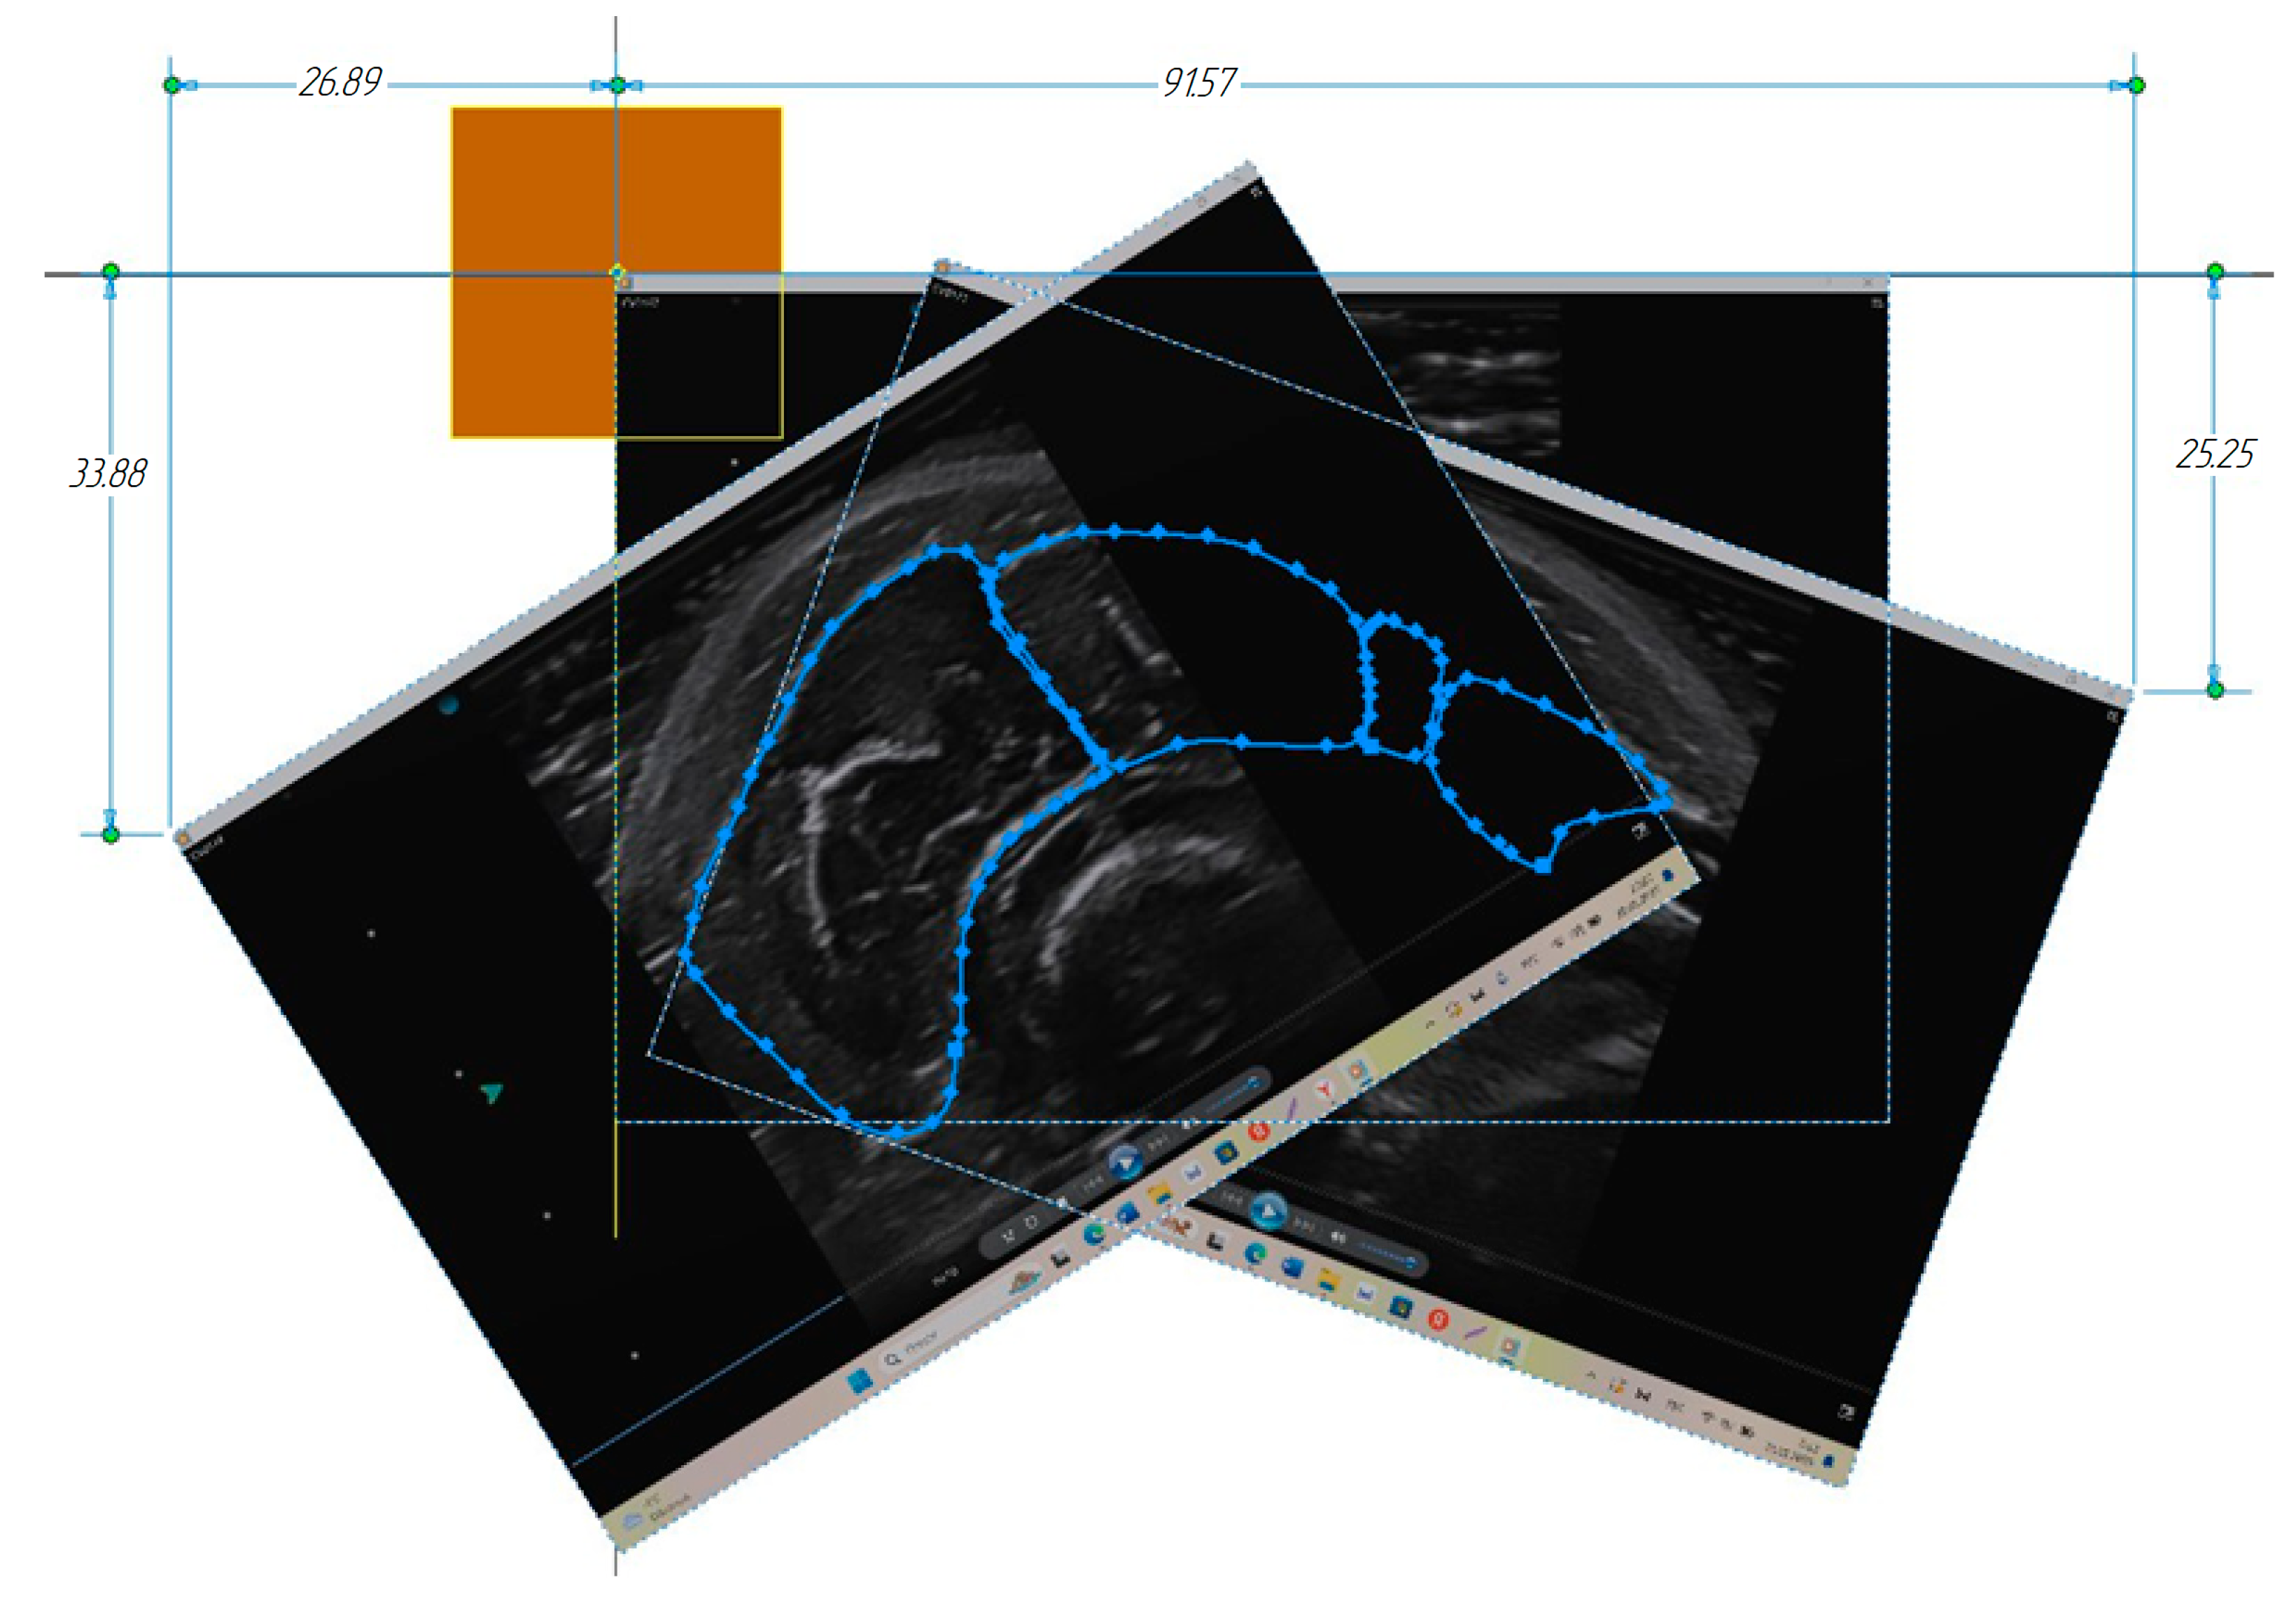

3.1. Construction of the Forearm Muscles’ Volumetric Models

3.2. Verification of the Methodology for Constructing the Soft Tissue Volumetric Models